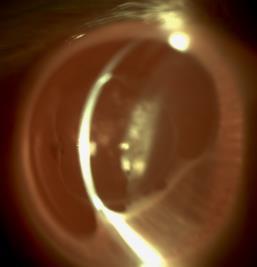

The IOL’s design contributes to its ability to deliver a continuous range of vision and low dysphotopsias, Dr McCabe said. It consists of a biconvex aspheric optic with a 1.2mm central zone with -0.15 microns of spherical aberration across its full dioptre range. Add powers are +1.6D for intermediate and +3.1D for near vision. The lens provides 0.2 logMAR or better visual acuity continuously across 4.0D of depth.

The anterior diffractive surface is apodized, with 22 steps in the central 4.5mm. The diffractive steps gradually decrease in height toward the periphery. This allows for an asymmetric distribution of light, with an even distribution in photopic conditions with 2-3mm pupil and distance vision prioritised in mesopic conditions with 3.5mm pupil or larger.

Proprietary technology reduces the profile of the diffractive edges, enhancing visual clarity and minimising glare and halos. The lens also comes with toric corrections available down to less than 0.75D cylinder.